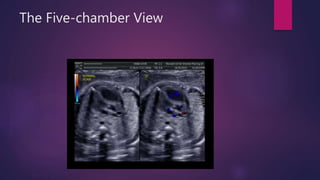

The Five-chamber View

Five-chamber view of the fetal heart demonstrating the

continuity of the posterior wall of the aorta with the mitral valve (small

arrows) and the continuity of the anterior wall of the ascending aorta

(AAo) with the ventricular septum (asterisks). The inflow and outflow

components of the left ventricle (LV) are seen in one view (open arrow).

The right and left superior pulmonary veins (RSPV, LSPV) enter the

posterior wall of the left atrium at this level. RV, right ventricle; LA, left

atrium; DAo, descending aorta; L, left.

Five-chamber view of the fetal heart demonstrating the wide

angle between the direction of the ventricular septum and the anterior

wall of the ascending aorta (AAo). This important anatomic observation

is commonly absent in conotruncal malformations. LV, left ventricle; RV,

right ventricle; LA, left atrium; DAo, descending aorta; L, left.

Role of Color Doppler: Image planes

 Five-chamber View:

 Demonstrating aortic blood flow in

blue color within the ascending aorta

or from a basal view (right side of

fetus) demonstrating aortic blood

flow in red color within the ascending

aorta

 Color Doppler of the five-chamber

view in the normal fetus shows the

septo-aortic continuity, the absence

of turbulences in systole, and

insufficiency in diastole across the

aortic valve